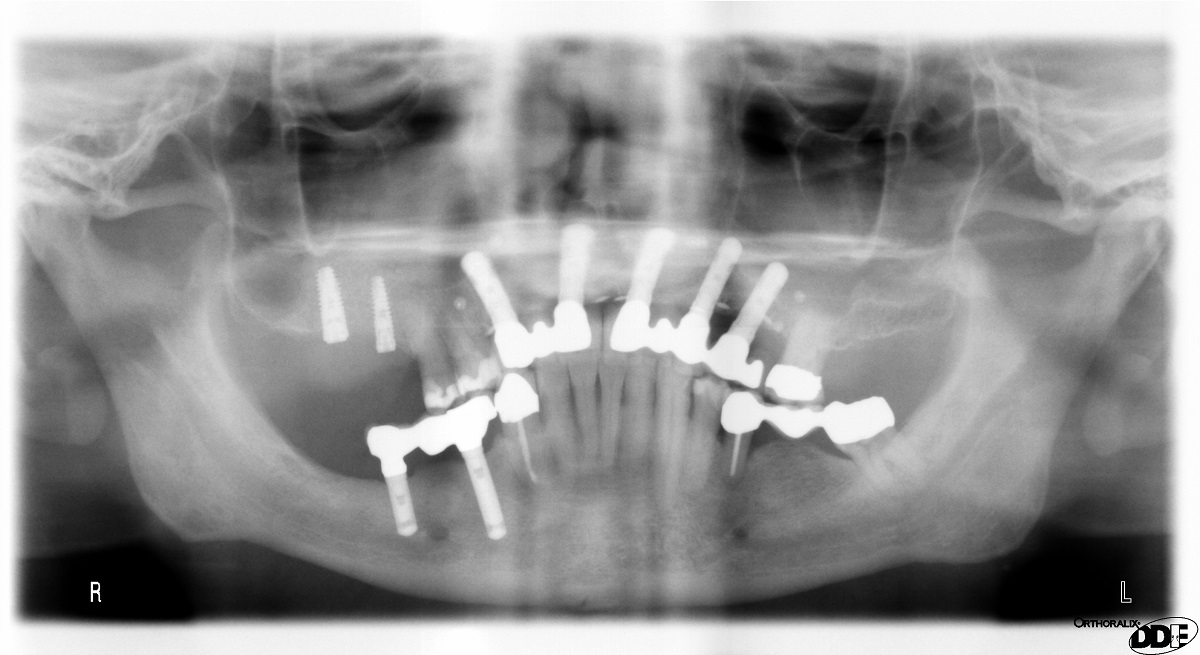

11/14 - OPG control of implant insertion

Two-stage sinus lift with maxresorb® & collprotect® - Dr. S. Kistler

14/14 - x-ray control after uncovering showing dense regeneration of the graft material